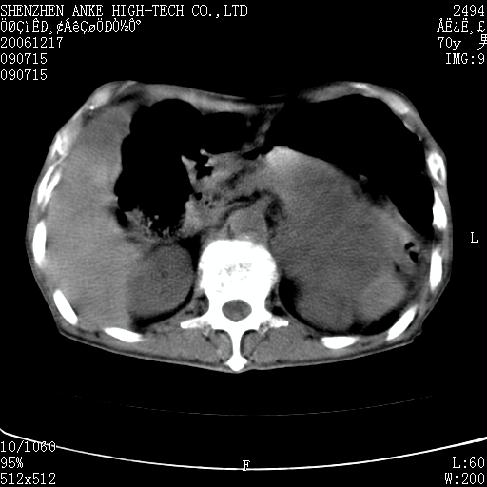

患者:男,70岁,腹部疼痛待查.b超见左肾脏占位待排.因为患者经济条件不好,没有做增强.

支持胰腺癌伴肝转移;左肾囊肿?

胰尾与左肾上缘部位见有一肿块影,密度不均匀,周围边界不清晰,与胰腺相连,与左肾边界不清,肝脏内见有多发低密度影,考虑胰尾癌伴左肾侵犯并肝内转移。最好是做个增强。

考虑:1,胰腺癌伴肝转移;2,左肾小囊肿。

与胃、脾及左肾之间见一巨大肿块影,其内密度不均,边界欠清,与胰腺关系密切。肝实质内见多个类圆形低密度灶,边界较清。符合胰腺癌并肝转移表现。

考虑:1,胰腺癌伴肝转移;2,左肾小囊肿. 3胰腺病变与左肾分界不清,肾脏可能受累。

与胃、脾及左肾之间见一巨大肿块影,其内密度不均,边界欠清,与胰腺关系密切。肝实质内见多个类圆形低密度灶,边界较清。符合胰腺癌并肝转移表现。

同意胰尾部癌累及左肾前,肝多发转移,左肾小囊肿。

胰尾与左肾上缘部位见有一肿块影,密度不均匀,周围边界不清晰,与胰腺相连,与左肾边界不清,肝脏内见有多发低密度影,考虑胰尾癌伴左肾侵犯并肝内转移。最好是做个增强。